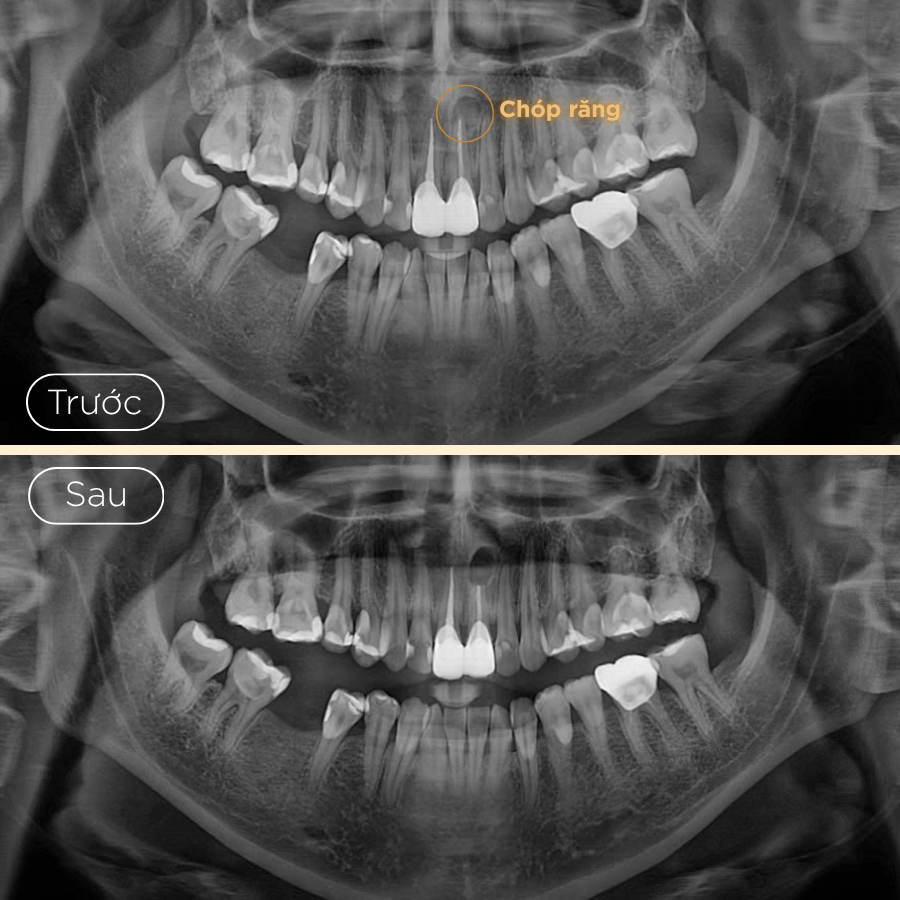

- 1. Khám và tư vấn: Bác sĩ sẽ thăm khám lâm sàng và chụp X-quang để xác định mức độ nhiễm trùng và vị trí chính xác của vùng viêm. Điều này giúp bác sĩ lên kế hoạch phẫu thuật một cách chi tiết và an toàn.

- 3. Gây tê, tiếp cận và cắt chóp chân răng: Trước khi bắt đầu quy trình, vùng cần điều trị sẽ được gây tê để đảm bảo bạn không cảm thấy đau hoặc khó chịu trong suốt quá trình điều trị. Bác sĩ sẽ tạo đường vào vị trí chóp răng bị nhiễm trùng, loại bỏ khoảng 2mm phần chóp răng, đồng thời làm sạch mô viêm xung quanh.

- 4. Trám ngược chóp răng và khâu đóng vết mổ: Sau khi vùng viêm đã được làm sạch, phần cuối của ống tủy sẽ được trám bít ngược lại bằng vật liệu chuyên dụng để ngăn chặn sự tái nhiễm trùng. Vết mổ sẽ được khâu đóng và lành lại trong vài tuần sau đó.